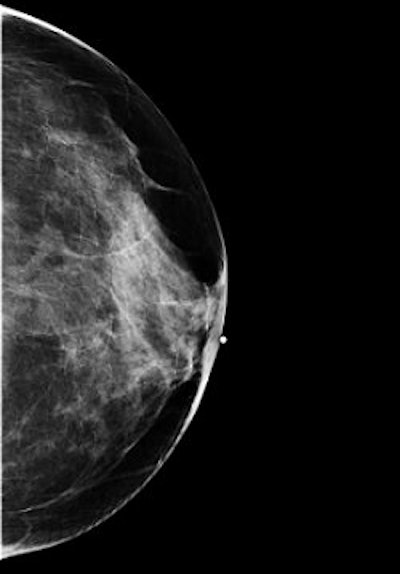

Mammography: CC view

![]() |

| Above, left CC ID view. Below, left CC view with implant. Images courtesy of Tammy Coryell. |